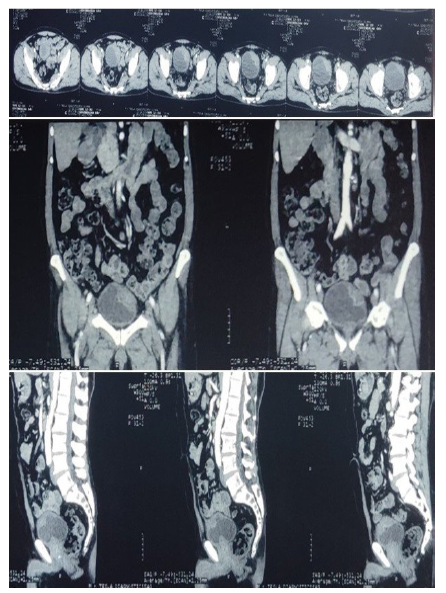

Contrast enhanced CT scan of KUB region revealed an irregular, heterogeneously enhancing lesion measuring 5.2 X 4.8 X 2.5 cm, arising from the anterior and left lateral walls of the urinary bladder. The differential diagnosis included carcinoma of the bladder (Figure 2).